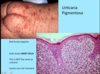

A: Describe Histology (3)

B: Dz

C: Location (2)

D: What’s this Dz caveat

A: image

B: Acanthosis Nigricans

C: Axilla and Neck Creases

D: THERE IS NO ACANTHOSIS ON HISTOLOGY

A: Describe Histology (3)

B: Dz

C: Location (2)

D: What’s this Dz caveat

A: image

B: Acanthosis Nigricans

C: Axilla and Neck Creases

D: THERE IS NO ACANTHOSIS ON HISTOLOGY